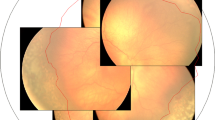

Table 1 summarizes the characteristics of the 56 infants, including their GA, BW, corrected weeks and body weight at first treatment, zone, stage, laser spot count, laser wavelength, and type of primary treatment. The mean ± standard deviation of the SE value at 1-year corrected age was −0.5 ± 3.0 dioptres (D). Table 2 provides the results of the linear regression analyses. In the univariable analysis, laser spot count (ß = −0.102 ± 0.039 D per 100 shots, p = 0.009, Fig. 2) and use of 808 nm laser (ß = −1.460 ± 0.564 D, p = 0.011) were significantly associated with the SE value.